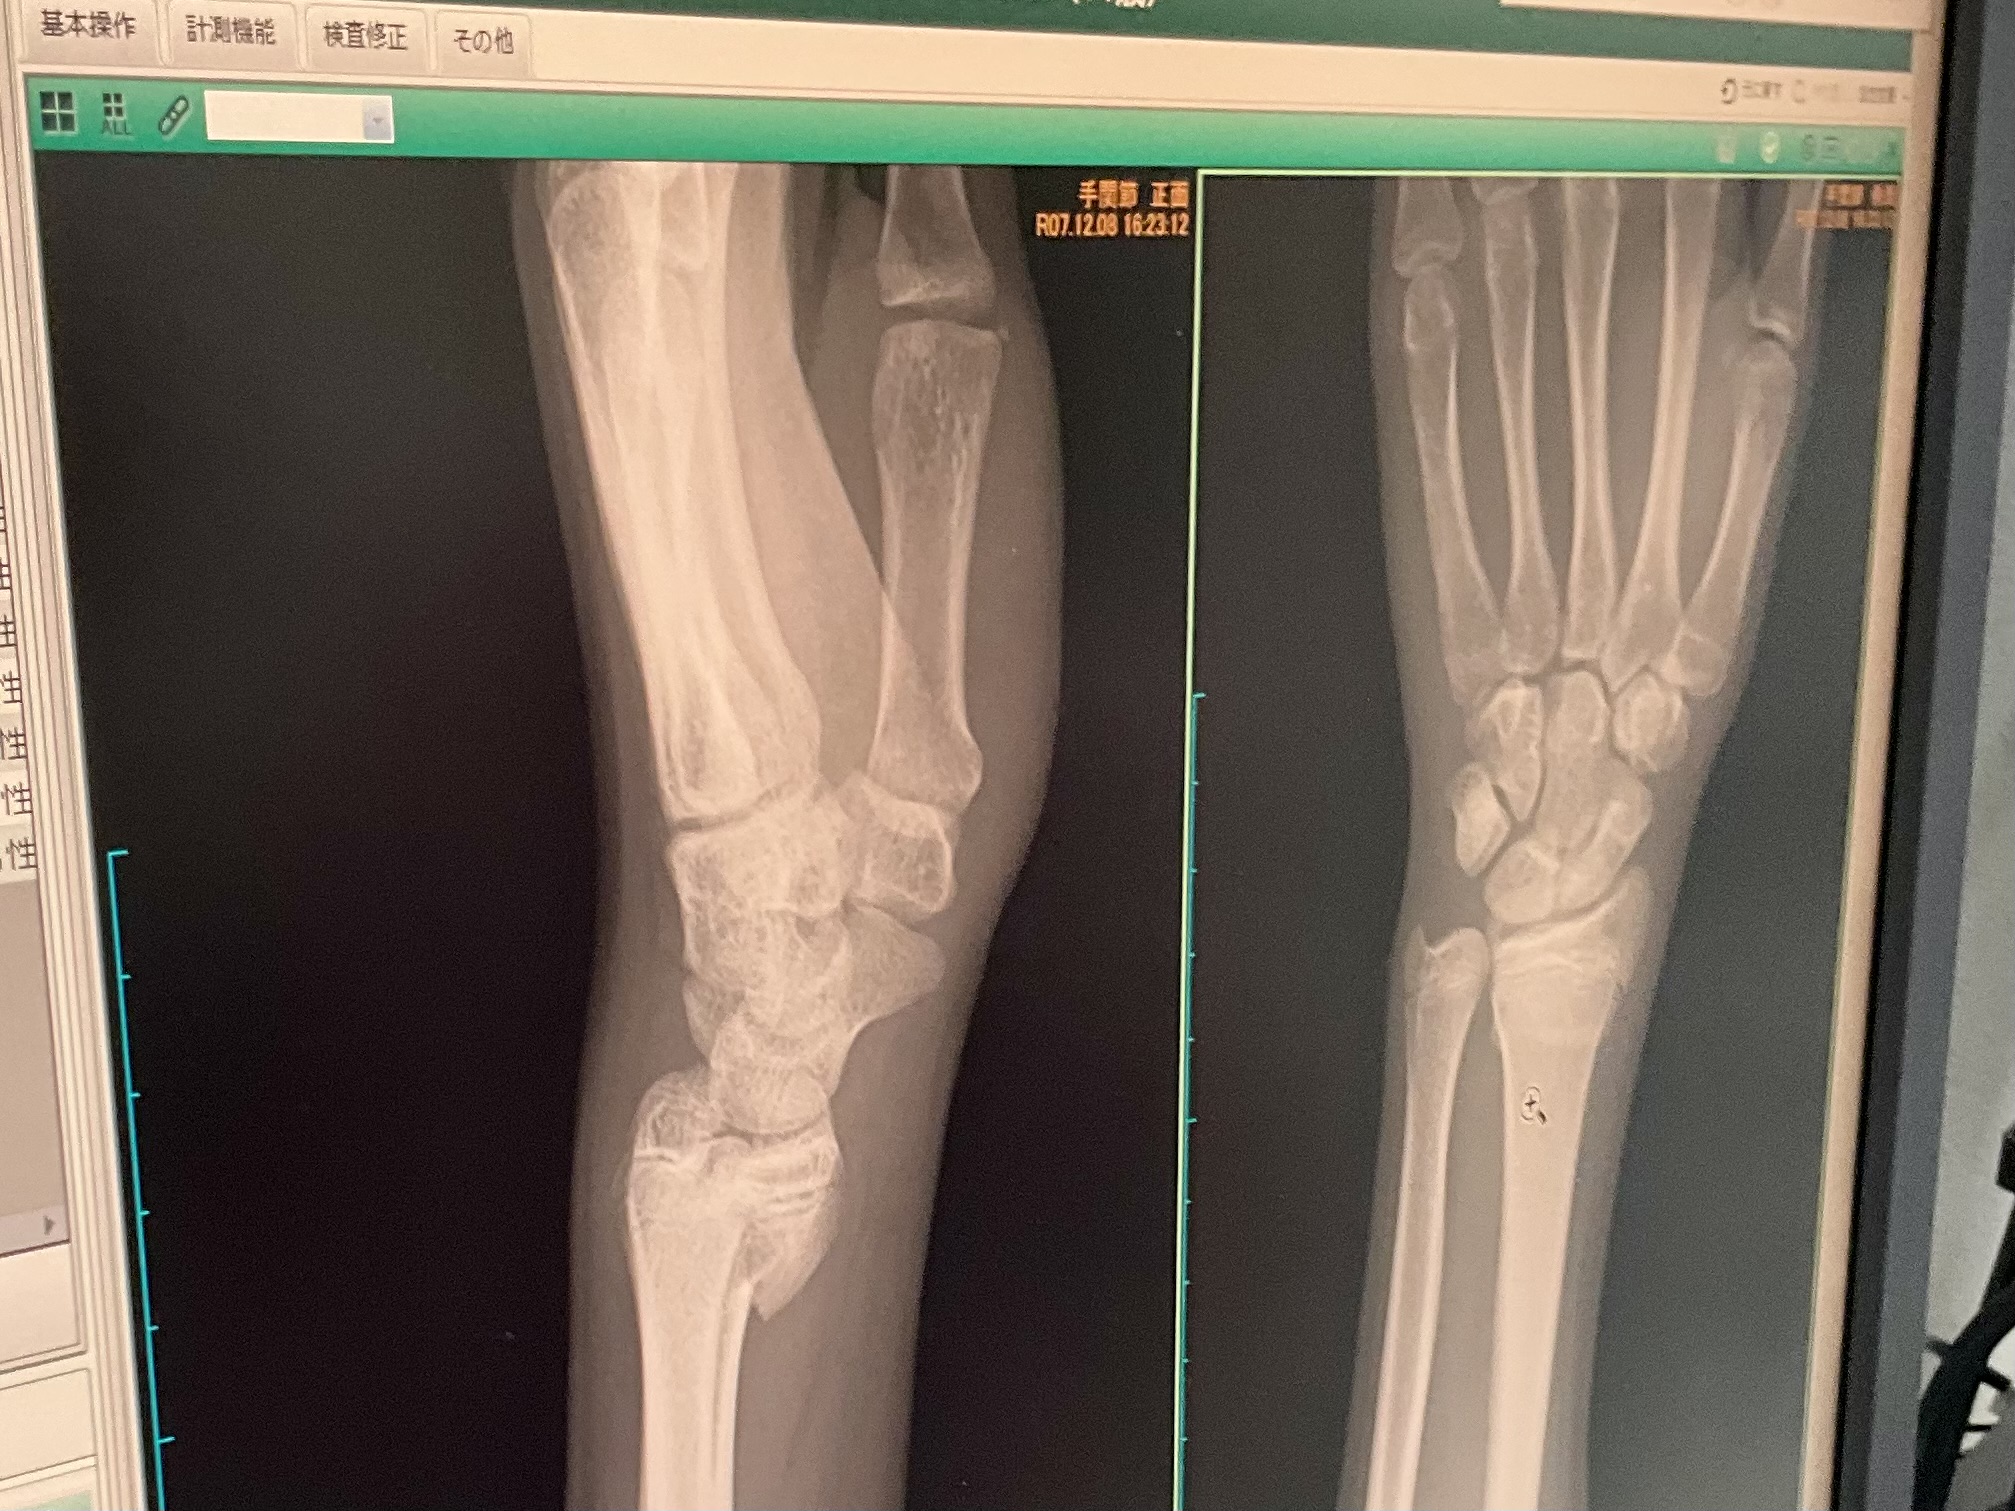

そんなこんな仕事していると、双子1号君から「迎えお願いします」とLINE。今日は放課後、委員会の会議があり、何時に終わるかはっきりしないので、スマホを持たせて連絡するように言ってあった。迎えに行ってそのまま整形外科へ。今日で骨折から一週間。擦り傷は治り、レントゲンを撮ってもらった結果、骨折も経過は順調なよう。それは何より。